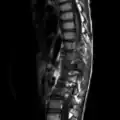

-

X-ray: osteoblastoma causing bent spine -

CT scan axial view: expansile osteoblastoma spine -

MRI scan osteoblastoma spine